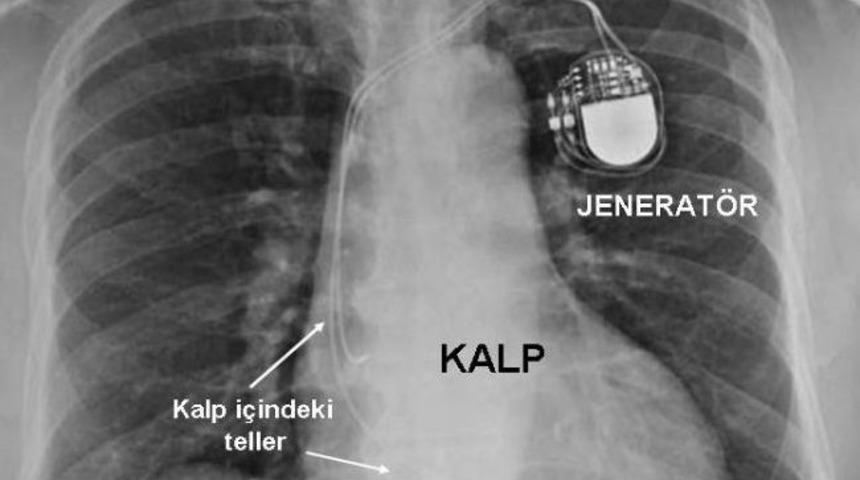

Kalp pilinin, kalbin çalışma hızının yavaşladığı, durakladığı ve kalp yetersizliği olan hastalara takıldığını anlatan Viva Kalp ve Beyin Sağlığı’ndan Kardiyoloji Uzmanı Prof.Dr. Ali Serdar Fak, “Kalbin çalışma hızının yavaşladığı, durakladığı durumlarda hastalar genellikle bayılan, kısa süreli şuur kaybı, dengesizlik yaşayan, göz kararması olan hastalardır. Kalp yavaşladığı zaman pil devreye girer ve elektrik vererek kalbi uyarır. Bir diğer grup kalp yetersizliği olan hastalardır. Kalbin yeterli kasılamadığı, kanı iyi pompalayamadığı durumlarda kalbin kasılma kuvvetini artırmak için takılan pillerdir” diye konuştu.

MR uyumlu pili deneyimli hekimlerin rahatlıkla takabileceğini belirten Prof.Dr. Fak, sözlerine şöyle devam etti: “Pil takıldıktan sonra hayat boyu çalışan cihaz değil. Takıldığında hastanın bünyesine uygun programının yapılması gerekir. Ameliyat sonrası ön ayardan sonra belli aralıklarla hastayı çağırırız ve en uygun ayarı yaparız. Çünkü hastalığın derecesi, vücudun ihtiyacı zamanla değişebilir. Hiç şikayeti olmasa bile hastanın 6 ayda bir kontrole gelmesi gerekir. 1960 yılında takılan piller buzdolabı büyüklüğündeydi fakat günümüzde 2-3 santimetre boyutundaki piller hastaya günlük yaşamında bir sıkıntı yaşatmıyor.”